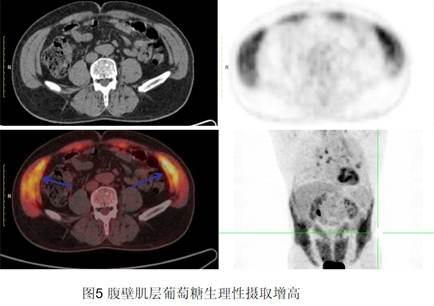

5、骨骼肌。正常情況下,骨骼肌核素攝取是很低的,但如果近期或檢查期間的過度運動后,會出現(xiàn)過度運動的肌群的高攝?。▓D5)而影響診斷,比如檢查期間交談可以出現(xiàn)咽喉部肌肉的FDG攝取,過分走動或運動導(dǎo)致部分骨骼肌的高攝取、過度用力呼吸造成的胸壁呼吸肌群的高攝取。所以在PET檢查前一天及當(dāng)天,要求避免做劇烈的運動及過度的說話,就可以避免出現(xiàn)骨骼肌的高攝取,從而造成與骨骼肌病變的鑒別困難。